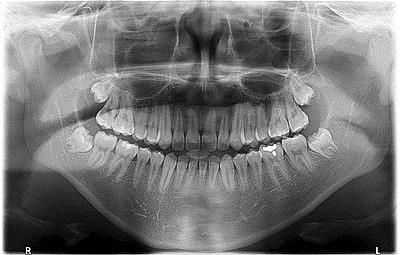

Unfortunately, there are times when a tooth has suffered so much destruction that it can not be saved and must be removed. We handle the majority of tooth extractions here at our office including some wisdom tooth extractions, however if needed we will refer some of the more complicated cases to an Oral Surgeon.